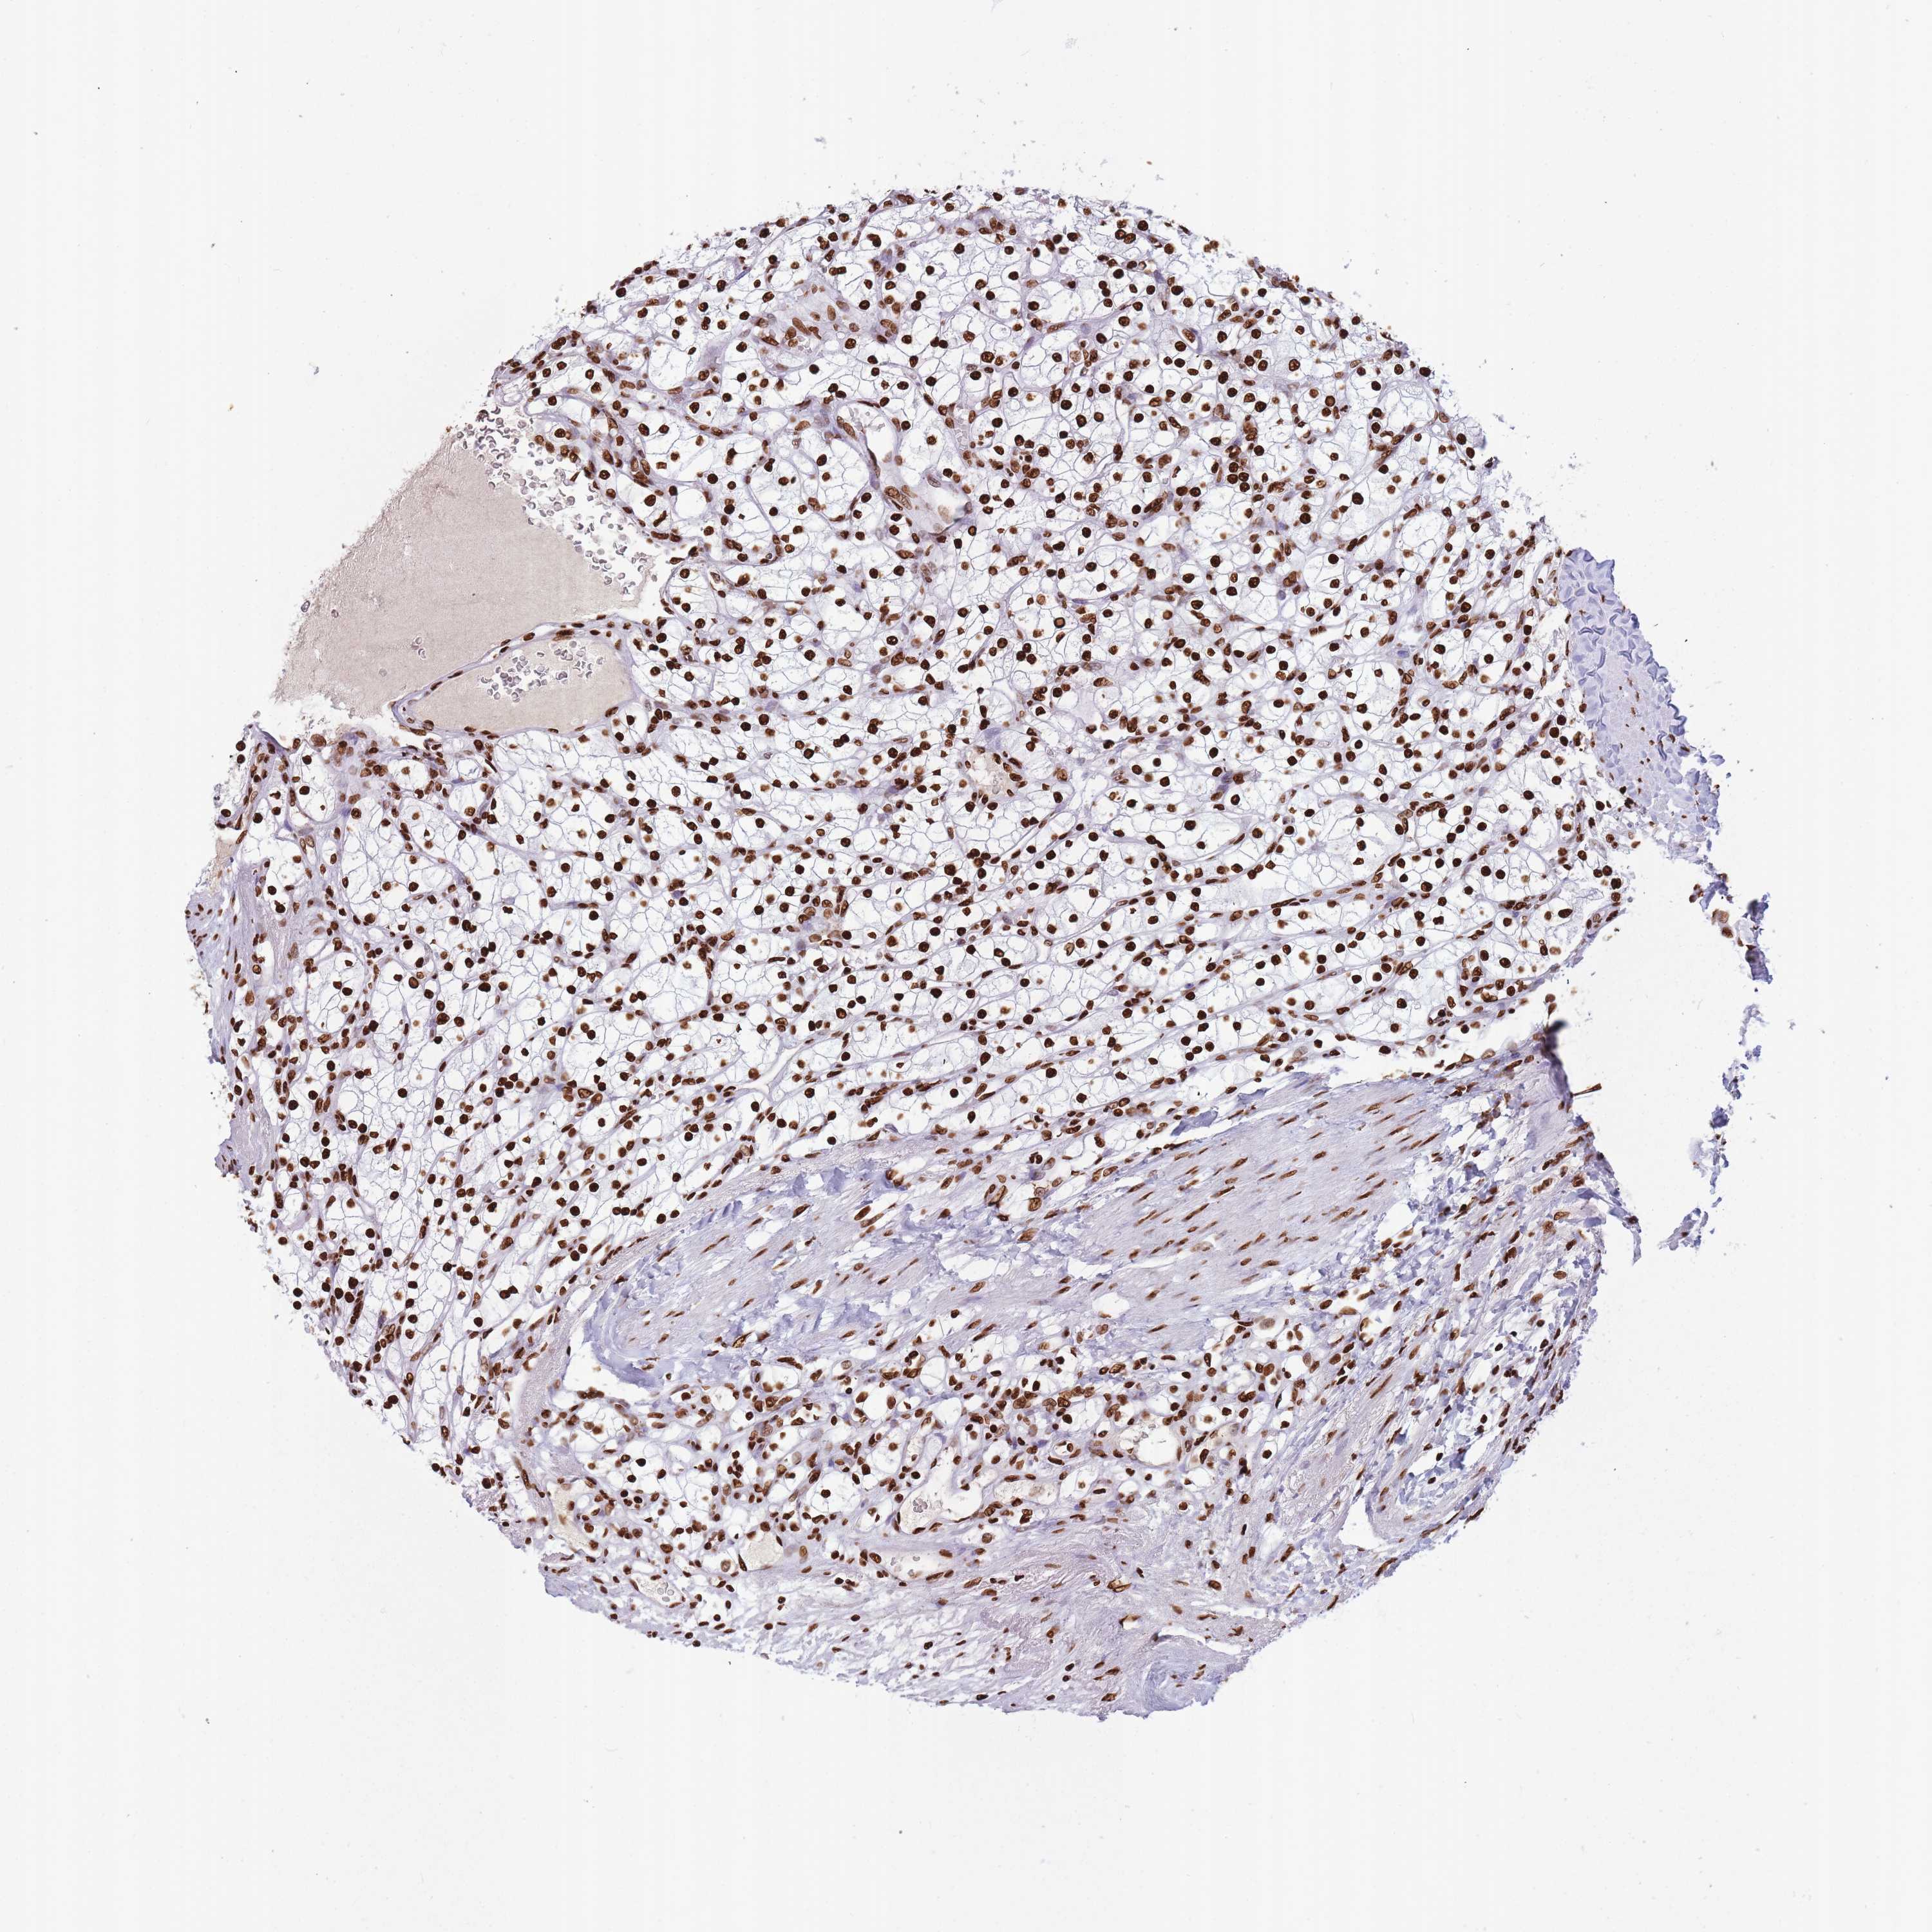

KIDNEY RENAL CLEAR CELL CARCINOMA (VALIDATION) - Interactive survival scatter ploti

The Survival Scatter plot shows the clinical status (i.e. dead or alive) for all individuals in the patient cohort, based on the same data that underlies the corresponding Kaplan-Meier plots. Patients that are alive at last time for follow-up are shown in blue and patients who have died during the study are shown in red.

The x-axis shows the expression levels (FPKM) of the investigated gene in the tumor tissue at the time of diagnosis. The y-axis shows the follow-up time after diagnosis (years). Both axes are complimented with kernel density curves demonstrating the data density over the axes. The top density plot shows the expression levels (FPKM) distribution among dead (red) and alive patients (blue). The right density plot shows the data density of the survived years of dead patients with high and low expression levels respectively, stratified using the cutoff indicated by the vertical dashed line through the Survival Scatter plot. This cutoff is automatically defined based on the FPKM cutoff that minimizes the p-score. The cutoff can be changed by dragging the vertical line or by entering a cutoff value in the square labeled "Current cut-off".

Under the Survival Scatter plot the p-score landscape (black curve; left axis) is shown together with dead median separation (red curve; right axis). Dead median separation is the difference in median mRNA expression between patients who have died with high and low expression, respectively. It is calculated as follows: median FPKM expression of dead patients with high expression - median FPKM expression of dead patients with low expression. This is intended to aid the user in visually exploring custom cutoffs and the associated p-scores and dead median separation.

Individual patient data is displayed and can be filtered by clicking on one or more of the category buttons on the top of the page. Categories describing expression level and patient information include: high, low, alive, dead, female, male and tumor stages. The scale of the x-axis can be toggled between linear and log-scale by clicking on the "x log" button. Mouse-over function shows TCGA ID, patient information and mRNA expression (FPKM) for each patient.

& Survival analysisi

Kaplan-Meier plots summarize results from analysis of correlation between mRNA expression level and patient survival. Patients were divided based on level of expression into one of the two groups "low" (under cut off) or "high" (over cut off). X-axis shows time for survival (years) and y-axis shows the probability of survival, where 1.0 corresponds to 100 percent.

HNRNPUL1 is not prognostic in Kidney Renal Clear Cell Carcinoma (validation)

Best expression cut offi

Based on the FPKM value of each gene, patients were classified into two groups and association between prognosis (survival) and gene expression (FPKM) was examined. The best expression cut-off refers the FPKM value that yields maximal difference with regard to survival between the two groups at the lowest log-rank P-value. Best expression cut-off was selected based on survival analysis .

When clicking on this number, the vertical dashed line indicating cut-off, the interactive survival plot, and the Kaplan-Meier curve will be adjusted to show results based on the best expression cut-off.

: 98.91

P scorei

Log-rank P value for Kaplan-Meier plot showing results from analysis of correlation between mRNA expression level and patient survival.

N/A

TCGA RNA samplesi

RNA-seq data is reported as average FPKM (number Fragments Per Kilobase of exon per Million reads), generated by the The Cancer Genome Atlas (TCGA) .

Normal distribution across the dataset is visualized with box plots, shown as median and 25th and 75th percentiles. Points are displayed as outliers if they are above or below 1.5 times the interquartile range. FPKM values of the individual samples are presented next to the box plot.

Average pTPM 89.2

Number of samples 100